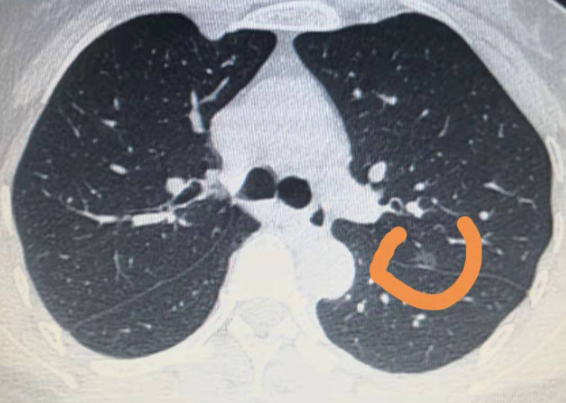

从患者身体CT扫描后获得的图像评估肺部良恶性结节的准确性相对有限,需要高水平医生的判断。即使高分辨率CT扫描结合高水平评估医生,准确率不高。率也很低。约 80%。理论上,只有采集肺结节细胞进行组织病理学检查,才能准确判断结节的良恶性。

一般建议患者每三个月复查一次CT扫描或PETCT,看结节是否有任何变化,如体积增大或减小、生长范围等。如果没有变化或者变化很小,可以延长审核时间,可以改为每六个月审核一次。如果重新评估后仍无变化,可延长至每年一次。由于有些肺癌的生长速度比较慢,比如透明的毛玻璃结节,几年来结果没有明显变化,因此需要长期随访排除肺癌,一般至少5年和需要多年的观察。

对于一些长期无法判断良恶性的肺部小结节,可进行穿刺活检进一步明确诊断,以免延误患者的诊治。穿刺活检的准确率可高达80%~90%,但由于病变部位或患者身体成分等因素,有时无法完全确诊。另外,穿刺活检毕竟有风险,不能因为担心而自愿去做。